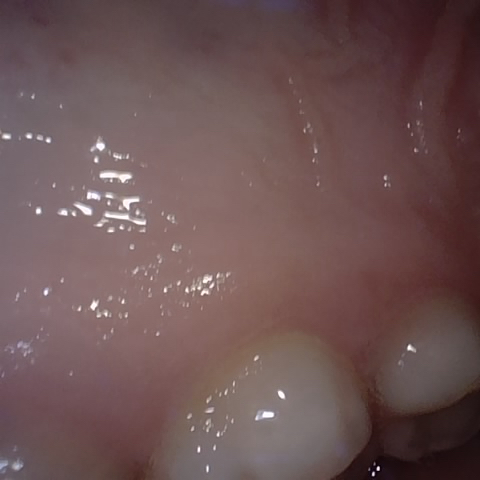

Incorrect Quality Level

The reference annotation for this image is

None

.

Please select the correct quality level.

Annotated as "Good"